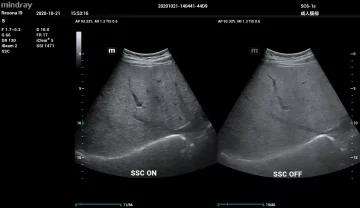

- SSC — технология автоматической оптимизации скорости ультразвуковых волн

SSC (Sound Speed Compensation) технология автоматической оптимизации скорости ультразвуковых волн